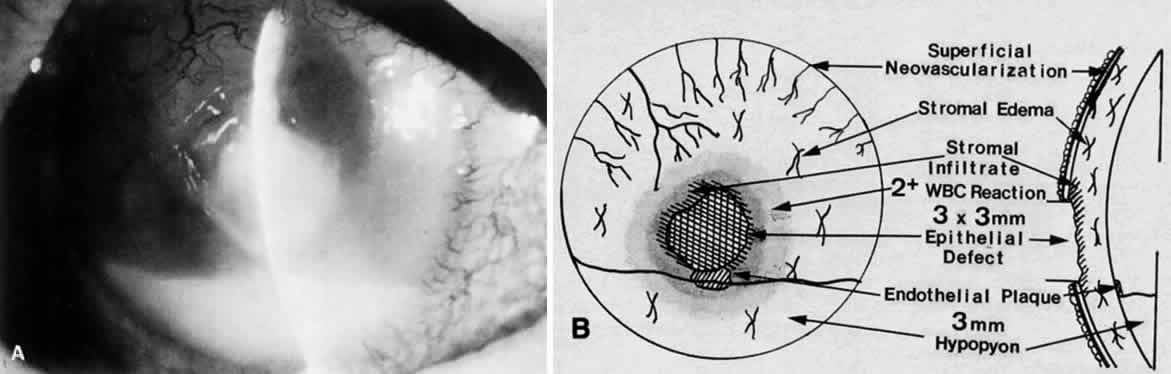

Clinically, the infected staphylococcal corneal ulcer presents with a yellow-white, well-demarcated area of infiltrate, which appears directly beneath an epithelial defect (Fig. 2). On occasion, multiple, small satellite lesions may develop. The infection may initially be superficial; however, if inadequately treated it can produce a mid to deep stromal abscess that may eventually lead to perforation. Stromal edema and white blood cell migration frequently surround the dense infiltrate and clear as the infection comes under control. Although there may be a marked anterior chamber reaction with hypopyon, the ulcer more frequently is indolent, with only a minimal inflammatory reaction.34

Corneal ulcers caused by S. pneumoniae are typically described as serpiginous or creeping and most often spread toward the center of the cornea. They are characterized by a gray-yellow disc-shaped ulcer with an overhanging margin at the advancing edge (Fig. 5). The ulcer usually progresses rapidly, extending into the deep stroma and often leading to corneal perforation. Extensive damage to corneal tissue, as well as a characteristic sterile hypopyon, are caused by the rapid production of bacterial exotoxin within the stroma.40,41